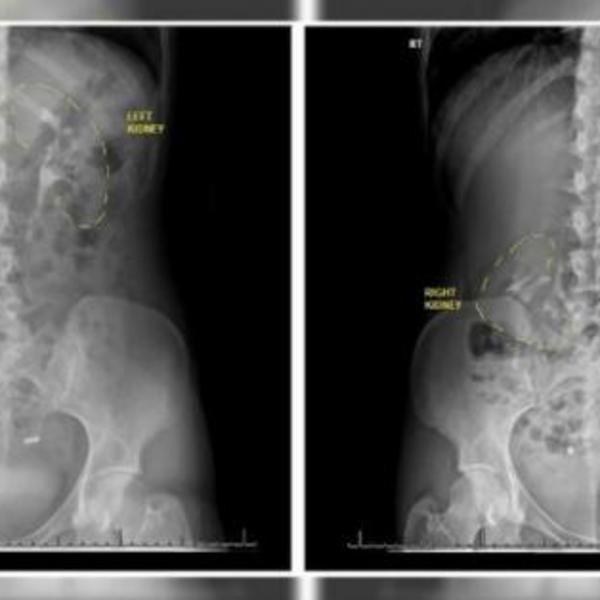

Petar Skendžić (69) iz Siriga već 37 godina živi sa transplantiranim bubregom koji mu dao otac.

Nakon što je dobio očev bubreg koji mu je spasao život, Petar je pomislio da je mukama došao kraj, ali borba je tek tada počela.

Otac i sin su bili u istoj operacionoj sali sto do stola, jer je najbolje transplantirati bubreg kaže Petar, dok je bubreg još u funkciji. Čim su bubreg uključili u protok krvi, za pola sata je počeo da funkcioniše, što je lekarima ulilo nadu da će sve biti u redu.

- Imam na pameti da moj bubreg može svakog trenutka da otkaže jer je bubreg komplikovana mašina. Nakon toliko godina smanjuje se mogućnost odbacivanja, ali on nikada ne prestaje i uvek postoji mogućnost da otkaže. Može i noćas da otkaže i da se situacija okrene i da me nema u sekundi, ali i sa tim sam se pomirio - objašnjava Skendžić.